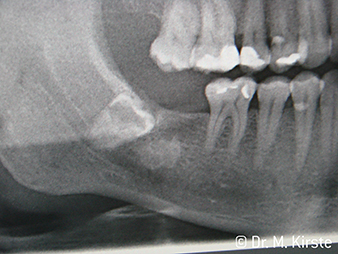

En la extracción de las muelas del juicio, los instrumentos quirúrgicos se encuentran con límites anatómicos: el carrillo supone un impedimento para las piezas de mano cuando la apertura bucal es pequeña, o bien el molar distal complica el acceso de la fresa para los contra-ángulos. En ambos casos, los nuevos contra-ángulos quirúrgicos de W&H ofrecen una solución inteligente – también en casos de separaciones amplias de dientes apicales.

Por primera vez, los instrumentos de transmisión WS-91 y WS-91 L G combinan las ventajas de las piezas de mano y los contra-ángulos quirúrgicos (Figura 1). Al haber ampliado el ángulo hacia el panel frontal entre la zona del mango y el eje de la fresa, se permite un buen acceso a la dentadura tanto bucal como oclusal (Figura 4). Los dientes desplazados pueden extraerse fácilmente (Figuras 6 y 7). Además, el doctor percibe mucho mejor el campo de operación que con los instrumentos disponibles anteriormente. A este respecto, el Dr. Mario Kirste de Fráncfort del Óder (Alemania) comenta: «Cuando giro ligeramente el cabezal del contra-ángulo, puedo trabajar de forma rápida y segura en la zona retromolar. El instrumento tiene el potencial de agrupar las diferentes posiciones necesarias tanto para los usuario de contra-ángulos como los de piezas de mano». (Figuras 2-5).